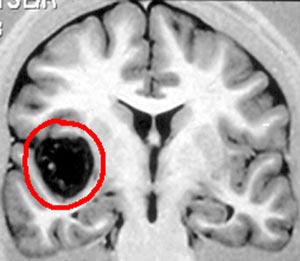

4b) Cavernoma

Figura 64 - Ressonância nuclear magnética pré-operatória.